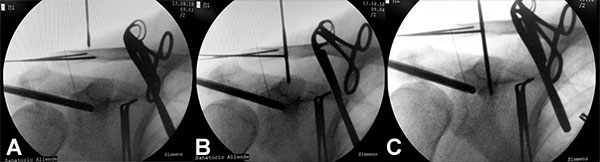

Con el paciente con bloqueo interescalénico y en posición de silla de playa con el brazo sin tracción en 10 a 20 grados de flexión y 20 a 30 grados de abducción, se introduce artroscopio por un portal posterior estándar y se realiza una artroscopia diagnostica en busca de lesiones asociadas. Se realiza un portal antero-inferior justo por encima del tendón del subescapular levemente más lateral de lo convencional con técnica de afuera-adentro y con dirección a la base de la coracoides, se realiza la colocación de cánula de 8,25 mm. Se realiza la apertura del intervalo de los rotador con shaver y electro bisturí artroscópico hasta la visualización de la punta y la base de la coracoides. Luego realizamos un nuevo portal percutáneo anterosuperolateral con técnica de afuera adentro y lo establecemos como nuevo portal de visión. Completamos la exposición de la base de la coracoides en la unión con la cara anterior del omoplato (fig. 1A) Se introduce el compás guía para AC TightRope o sistema DogBone por el portal antero inferior y se lo posiciona centrado en la coracoides a nivel de la unión de la base de la coracoides con la cara anterior del omoplato en 70 a 90 grados de angulación (fig. 1B). Se realiza un abordaje longitudinal de 2 a 3 cm a nivel del foco de fractura, se limpia foco de fractura, se reseca tejido interpuesto y se realiza la reducción de la fractura y fijación transitoria con clavijas de 1,6 mm, se controla reducción por radioscopia (fig. 2). La guía del compas es posicionada entre 25 y 30 mm medial a la articulación acromioclavicular y centrada en la clavícula para evitar lesionar la cortical anterior o posterior. Se realiza la perforación de la clavícula y la coracoides con drill pin canulado de 3 mm atravesando 4 corticales para pasar a través de la clavícula y coracoides visualizando posicionamiento por radioscopia, y control por artroscopia de la salida del drill pin en la base de la coracoides, se retira el pin del drill canulado y se introduce un alambre de nitinol que se recupera por el portal antero inferior (fig 3). Se retira el drill canulado dejando el alambre de nitinol. Si vamos a utilizar sistema AC TightRope debemos desmontar ambos botones del FiberWire y montar dos suturas FiberTape en el botón longitudinal para pasar a través del túnel coracoideo y clavicular solo los cuatro extremos suturas. Se montan los 4 extremos de las suturas FiberTape del implante subcoracoideo en el alambre de nitinol y se realiza el pasaje del mismo de distal a proximal (fig. 4). Bajo visión artroscópica directa se comprueba el pasaje y posicionamiento del botón subcoracoideo (fig. 5). Se realiza la reducción de la fractura aplicando presión inferior sobre el fragmento proximal de la fractura y contrapresión superior desde el codo para ayudar a reducir la fractura. Una vez reducida la fractura bajo control radioscópico se completa la fijación del botón clavicular del sistema AC TightRope o DogBone y con sutura FiberTape transósea se incorpora el fragmento distal de la fractura a la reconstrucción (fig. 6).

Figura 2: Abordaje longitudinal de 2-3 cm a nivel del foco de fractura. Se realiza reducción de la fractura y fijación transitoria con clavijas de 1,6 mm.Abordaje longitudinal de 2-3 cm a nivel del foco de fractura. Se realiza reducción de la fractura y fijación transitoria con clavijas de 1,6 mm.

Figura 3: Control Radioscópico de drill canulado